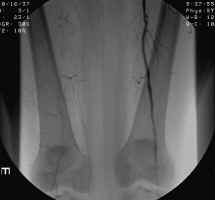

The images shown demonstrate increased collateral vessels and an occluded SFA on the

right. These images are critical to help the surgeon decide between possible

treatment options (bypass, angioplasty, or amputation). Clinical exam and imaging

aid in the decision as to what level to select when amputation is deemed necessary.